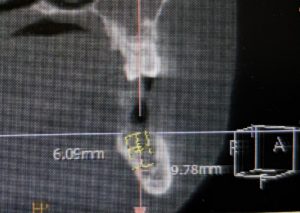

午前中のオペ

左下6番欠損に対してストローマンBLXインプラントを植立しました。

直径6.5×6mm 骨が少なくても刺さりますね。